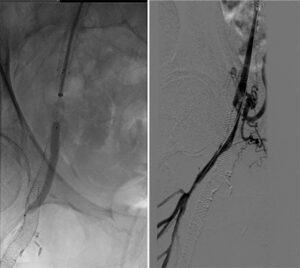

Figure 4. Follow-up angiogram at 40 months (new stent shown with white arrows; occluded stent with black arrows)

Angiography performed 3 years and 8 months following the procedure demonstrated excellent patency of the DBS (Picture). Interventions were performed at sites other than the double-barrel stent.